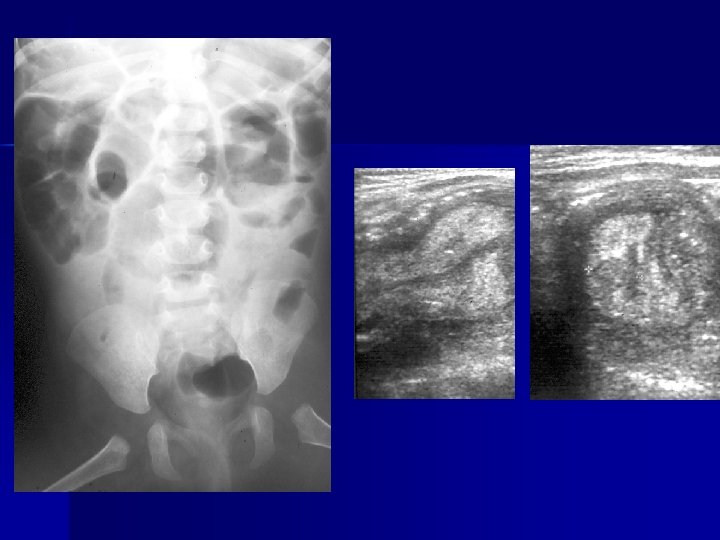

ECOGRAFIA E’ l’esame più utilizzabile nella patologia addominale Possiede: elevata specificità(91 -96%) valore predittivo più elevato versus esame clinico(88>69%).

Ecografia n n E’ una tecnica accurata nell’evidenziare : infiammazioni peri-appendicolari, ileite terminale, adenite mesenterica. invaginazione intestinale patologia testicolare e ginecologica Il limite di questa tecnica è che la qualità della lettura è molto legata alla capacità ed all’esperienza dell’operatore

Adenite mesenterica (US)

SEU: pseudoinvaginazione intestinale

Vasculite di S-H